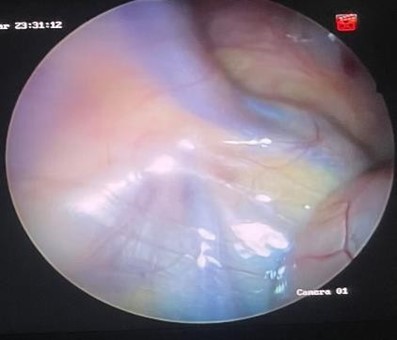

Figura 1. Anillo inguinal izquierdo cerrado

Figura 2. Anillo inguinal derecho permeable